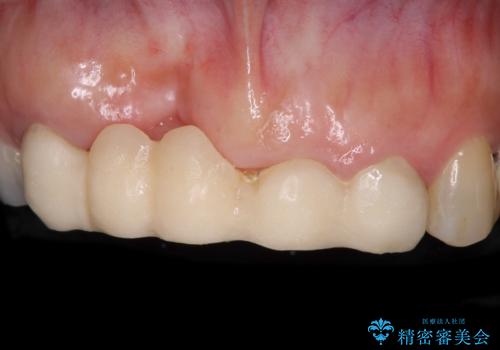

歯周病改善のための総合歯科治療